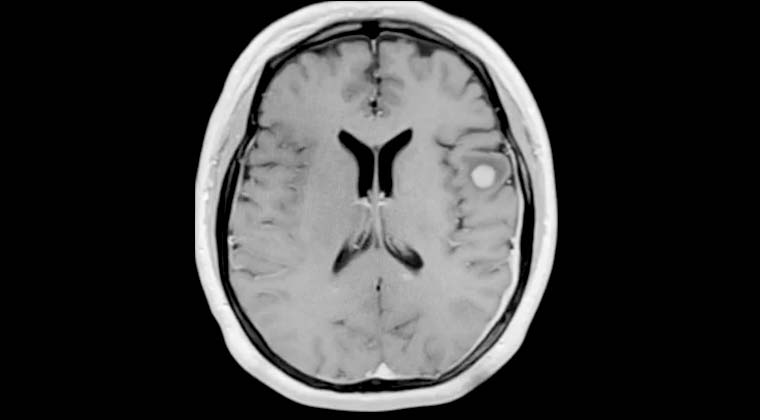

Рисунок 1: Первое лечение Гамма-ножом 26.04.2021

Рисунок 2: Второе лечение Гамма-ножом 03.11.2021

Рисунок 3: МРТ контроль 22.02.2023 — видно значительное сокращение аномальных сосудов, приступы прекратились.